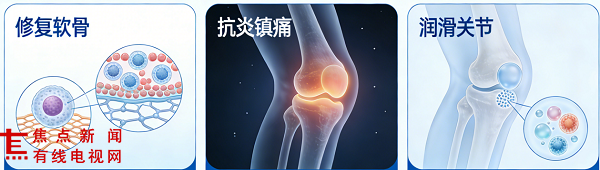

骨素宁非变性II型氨糖软骨肽片的核心优势,在于集结了多种经研究证实的高活性原料,且含量配置远超行业常规标准:非变性II型胶原蛋白(UC-II)60mg /片、N-乙酰氨基葡萄糖(NAG)500mg /片、软骨肽 250mg /片、透明质酸钠 100mg /片,搭配弹性蛋白、乳矿物盐(乳钙)、酪蛋白磷酸肽形成科学复配体系。

其中,非变性II型胶原蛋白通过低温萃取技术完整保留天然三螺旋结构,作为关节软骨核心组成成分,被哈佛医学院研究证实可通过 “口服免疫耐受” 机制调节免疫反应,为软骨修复创造有利条件,其抗炎相关研究效果是传统氨糖+软骨素组合的2.6倍。[1]

透明质酸钠作为关节滑液核心成分,可使关节摩擦系数降低67%,为关节活动提供高效润滑保护。[3]

软骨肽与弹性蛋白的协同作用,进一步完善了关节组织营养供给,多项研究提示该类原料组合对关节软骨保护、炎症因子调节、关节润滑改善具有积极意义。[4]